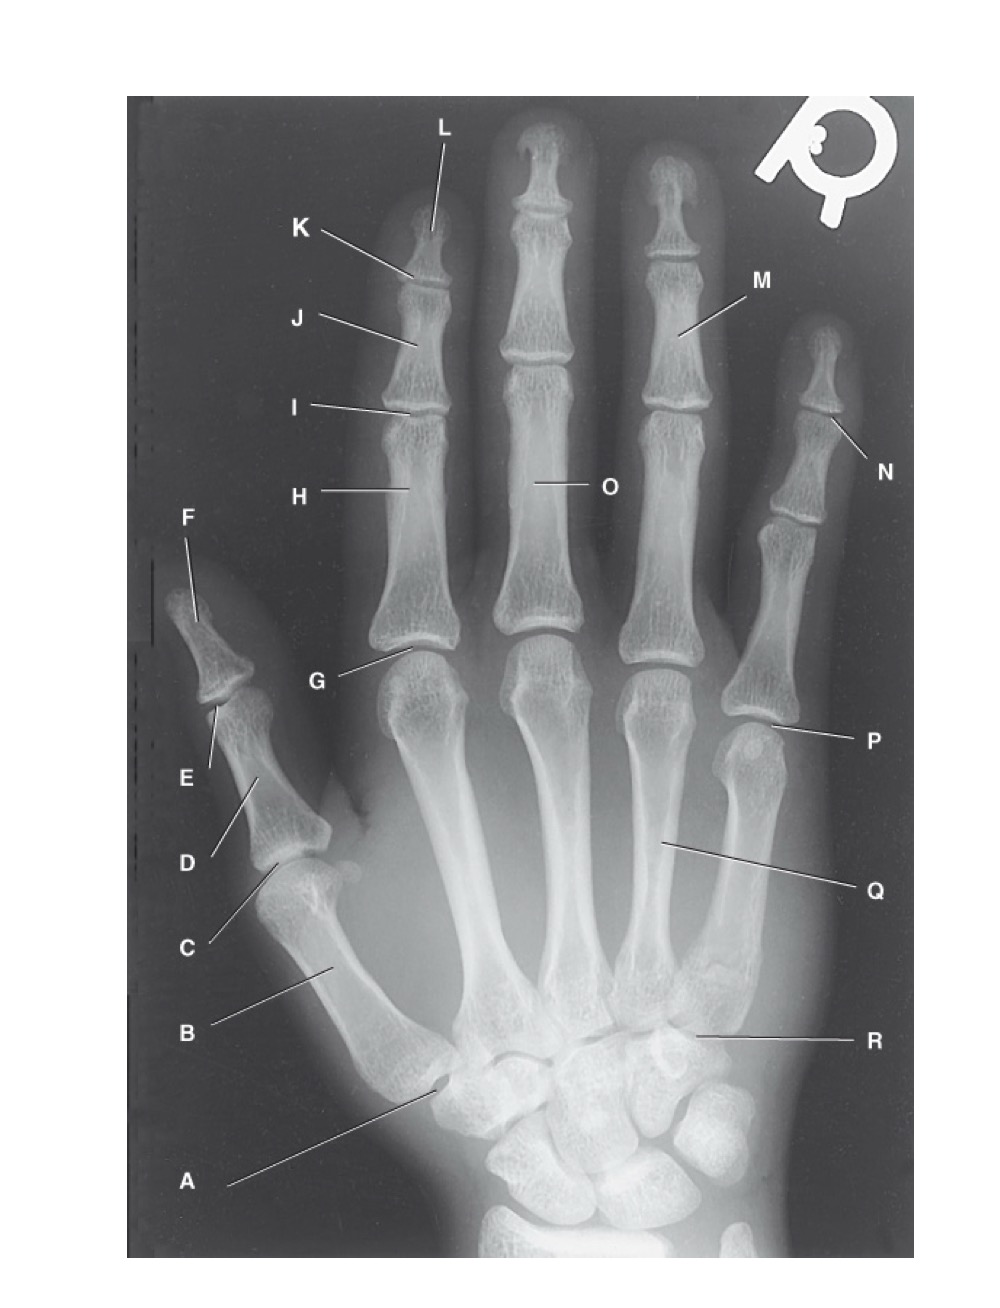

<p>identify A</p>

identify A

first carpometacarpal

<p>B?</p>

B?

first metacarpal

<p>C?</p>

C?

first metacarpophalangeal joint

<p>D?</p>

D?

proximal phalanx of the first digit

<p>E?</p>

E?

interphalangeal joint of the first digit

<p>F?</p>

F?

distal phalanx of the first digit

<p>G?</p>

G?

second metacarpophalangeal joint

<p>H?</p>

H?

proximal phalanx of the second digit

<p>I?</p>

I?

proximal interphalangeal joint of the second digit

<p>J?</p>

J?

middle phalanx of second digit

<p>K?</p>

K?

distal interphalangeal joint of second digit

<p>L?</p>

L?

distal phalanx of second digit

<p>M?</p>

M?

middle phalanx of the fourth digit

<p>N?</p>

N?

distal interphalangeal joint of fifth digit

<p>O?</p>

O?

proximal phalanx of third digit

<p>P?</p>

P?

fifth metacarpophalangeal joint

<p>Q?</p>

Q?

fourth metacarpal

<p>R?</p>

R?

fifth carpometacarpal joint